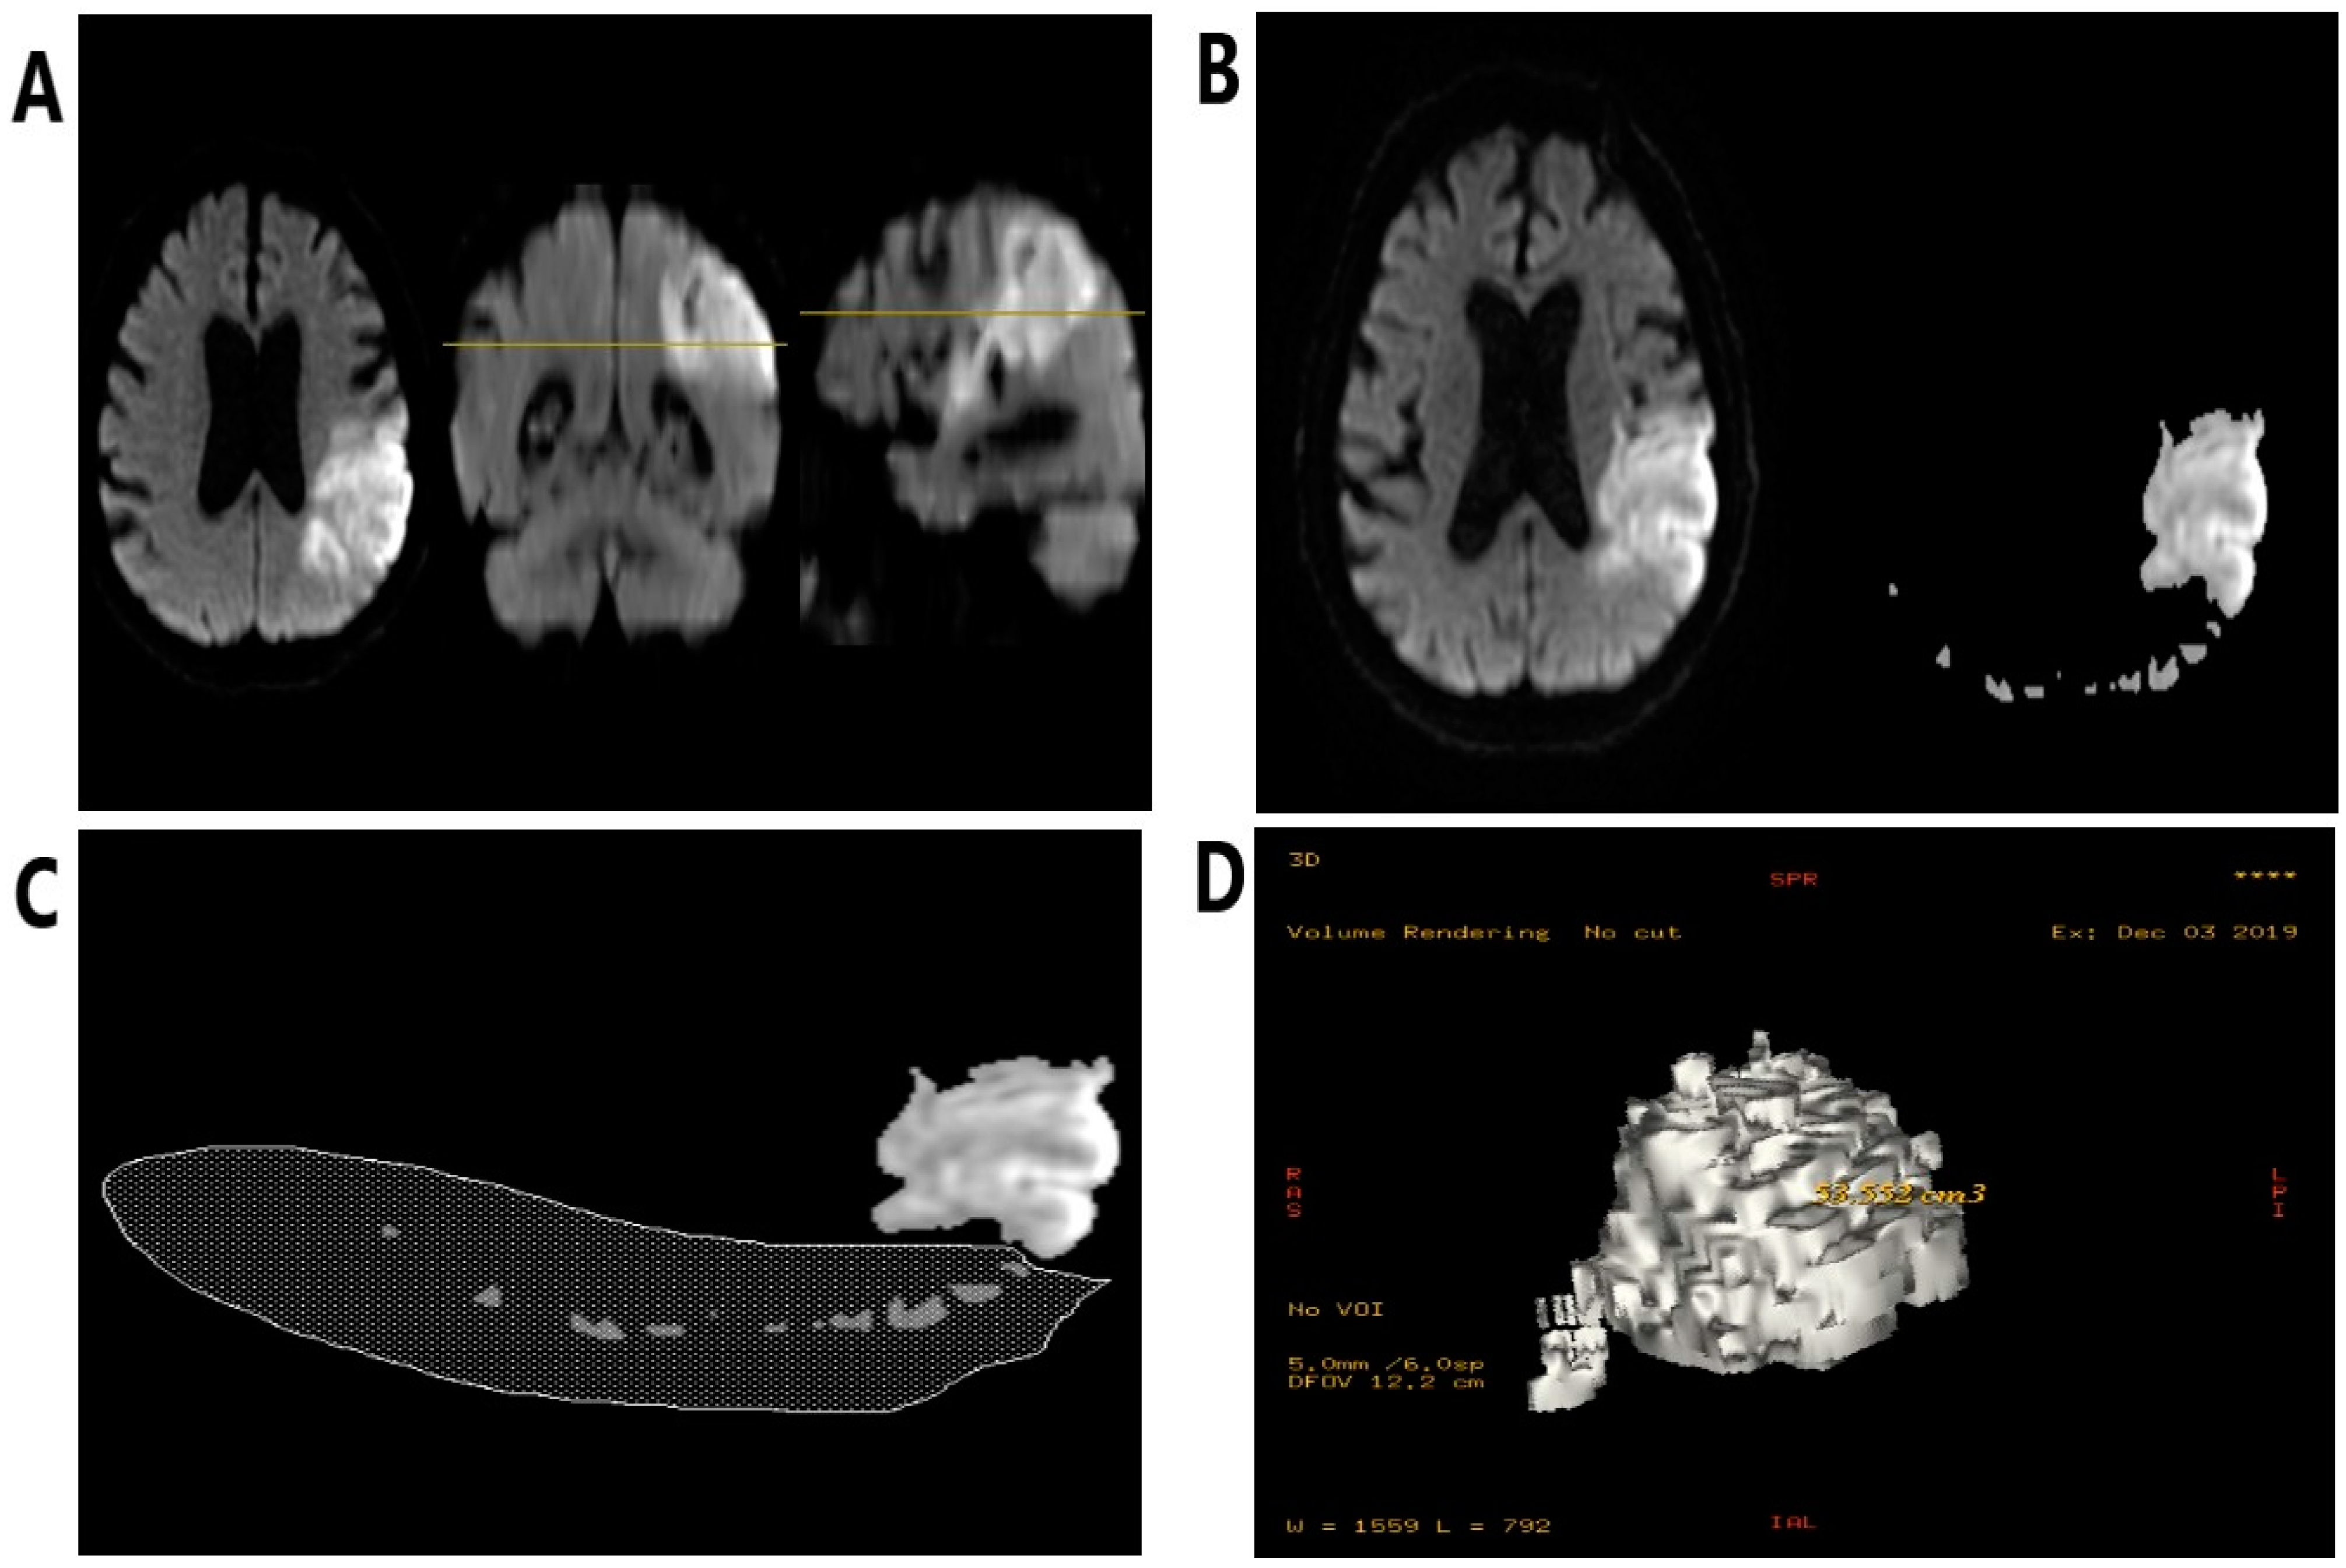

2.3. The Volumetric Evaluation